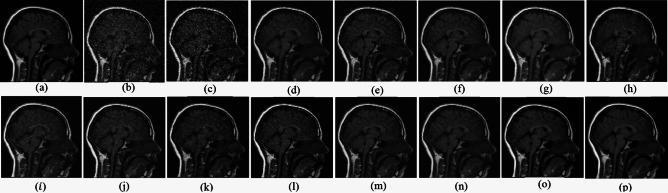

Medical imaging systems such as computed tomography (CT) and magnetic resonance imaging (MRI) are vital tools in clinical diagnosis and treatment planning. However, these modalities are inherently susceptible to Gaussian noise introduced during image acquisition, leading to degraded image quality and impaired visualization of critical anatomical structures. Effective denoising is therefore essential to enhance diagnostic accuracy while preserving fine details such as tissue textures and structural boundaries. This study proposes a robust and efficient denoising framework specifically designed for CT and MRI images corrupted by Gaussian noise. The method integrates a cluster-wise principal component analysis (PCA) thresholding approach guided by the Marchenko-Pastur (MP) law from random matrix theory and a non-local means algorithm. Noise level estimation is achieved globally by analysing the statistical distribution of eigenvalues from noisy image patch matrices and leveraging the MP law to accurately determine the Gaussian noise variance. An adaptive clustering technique is employed to group similar patches based on underlying features such as textures and edges and enables localized denoising operations tailored to heterogeneous image regions. Within each cluster denoising is performed in two stages where initially hard thresholding based on the MP law is applied to the singular values in the SVD domain to obtain a low-rank approximation that preserves essential image content while removing noise-dominated components. Residual noise in the low-rank matrix is then further suppressed through a coefficient-wise linear minimum mean square error LMMSE estimator in the PCA transform domain. Finally, a non-local means algorithm refines the denoised image by computing weighted averages of pixel intensities and prioritizing neighbourhood similarity over spatial proximity to effectively preserve edges and textures while reducing Gaussian noise. Experimental evaluations on CT and MRI datasets demonstrate that the proposed method achieves superior denoising performance while maintaining high structural similarity and perceptual quality compared to existing state-of-the-art approaches. The method demonstrates adaptability noise reduction capability and preservation of anatomical detail that make it well suited for precision critical medical imaging applications.

计算机断层扫描(CT)和磁共振成像(MRI)等医学成像系统是临床诊断和治疗规划中的重要工具。然而,这些模态在图像采集过程中固有地容易受到高斯噪声的影响,导致图像质量下降以及关键解剖结构的可视化受损。因此,有效的去噪对于提高诊断准确性同时保留诸如组织纹理和结构边界等精细细节至关重要。本研究提出了一种强大且高效的去噪框架,专门针对受高斯噪声破坏的CT和MRI图像设计。该方法集成了一种由随机矩阵理论中的马尔琴科 - 帕斯图尔(MP)定律引导的聚类主成分分析(PCA)阈值处理方法和一种非局部均值算法。通过分析噪声图像块矩阵的特征值统计分布并利用MP定律来准确确定高斯噪声方差,实现全局噪声水平估计。采用自适应聚类技术根据纹理和边缘等潜在特征对相似块进行分组,并针对异质图像区域进行局部去噪操作。在每个聚类中,去噪分两个阶段进行,首先在奇异值分解(SVD)域中基于MP定律应用硬阈值处理奇异值,以获得保留基本图像内容同时去除噪声主导成分的低秩近似。然后在PCA变换域中通过系数线性最小均方误差(LMMSE)估计器进一步抑制低秩矩阵中的残余噪声。最后,非局部均值算法通过计算像素强度的加权平均值并优先考虑邻域相似性而非空间邻近性来细化去噪图像,从而在减少高斯噪声的同时有效保留边缘和纹理。对CT和MRI数据集的实验评估表明,与现有的最先进方法相比,所提出的方法在保持高结构相似性和感知质量的同时实现了卓越的去噪性能。该方法展示了适应性降噪能力和解剖细节保留能力,使其非常适合精密关键的医学成像应用。